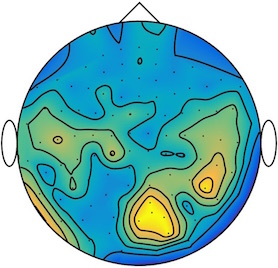

We applied our method to a magnetoencephalography (MEG) dataset. In this setup, brain activity of a subject is recorded (Elekta Neuromag, 306 sensors of which 204 planar gradiometers and 102 magnetometers, sampling frequency 1000Hz) while the subject reacted to the presentation of a target stimulus by pressing either the left or the right button.

Data is preprocessed applying signal space separation correction, interpolation of noisy sensors, and realignment of data into a subject-specific head position (MaxFilter, Elekta Neuromag). The signal was then filtered (low pass 40HZ), and artifacts such as blinks and heartbeats removed thanks to Signal-Space Projection using the Brainstorm software222http://neuroimage.usc.edu/brainstorm. The samples we used for our barycenter computations are an average of the norm of the two gradiometers for each channel from stimulation onto 50ms and the classes were left or right button.

This results in two classes of recordings, one for each pressed button. We aim at computing a representative activity map for each class using Wasserstein barycenters. For each class we have recordings each having samples located on the vertices of an hexahedral mesh of a hemisphere (corresponding to a MEG recording helmet). These recorded values are positive by construction, and we rescale them linearly to impose . Figure 6, top row, shows some samples from this dataset, displayed using interpolated colors as well as iso-level curves. The black dots represent the position of the electrodes on the half-sphere of the helmet, flattened on a 2-D disk.

We computed TV-regularized barycenters independently for each class by solving (16) with the TV regularization using the projected gradient descent method (22). We used a squared Euclidean metric (24) on the flattened hemisphere. Since the data is defined on an irregular graph, instead of (23), we use a graph-based discrete gradient. We denote the graph which connects neighboring electrodes. The gradient operator on the graph is

The total variation on this graph is then obtained by using , the norm, i.e. we use in (23).

Figure 6 compares the naive barycenters (i.e. the usual mean), barycenters obtained without regularization (i.e. ) and barycenters computed with an increasing regularization strength . The input histograms being very noisy, the use of regularization is important to make the area of significant activity emerge from the noise. The use of a TV regularization helps to keep a sharp transition between active and non-active regions.